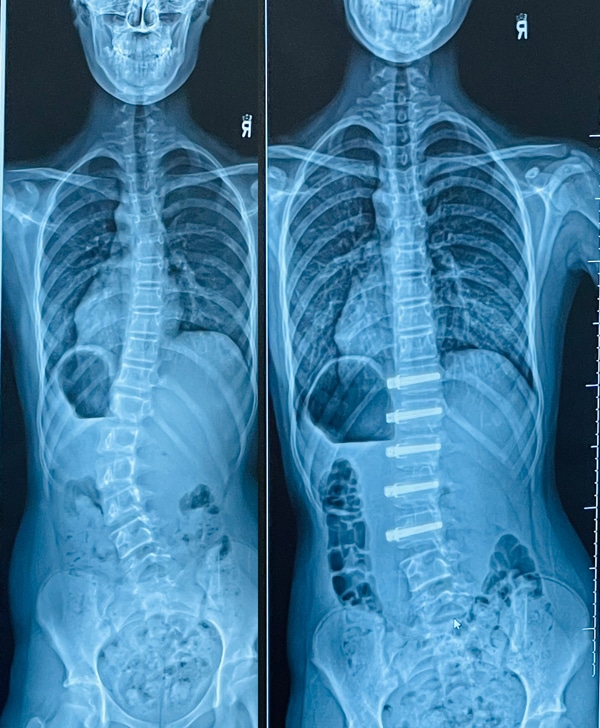

Then came a devastating diagnosis: scoliosis, an abnormal lateral curvature of the spine. with a 40-degree curve that was expected to worsen as she grew.

Images of Hazel’s spine before (left) and after the surgery.

Hazel faced a choice: wait and likely require full spinal fusion, which would severely restrict her range of motion, or undergo an innovative, still-rare procedure called Vertebral Body Tethering (VBT), which had only been performed roughly 300 times in Canada at that point.

In August 2022, just before Grade 9, Hazel underwent surgery. Screws and a tether were placed from L1 to L6 to gradually straighten her spine as she finished growing.